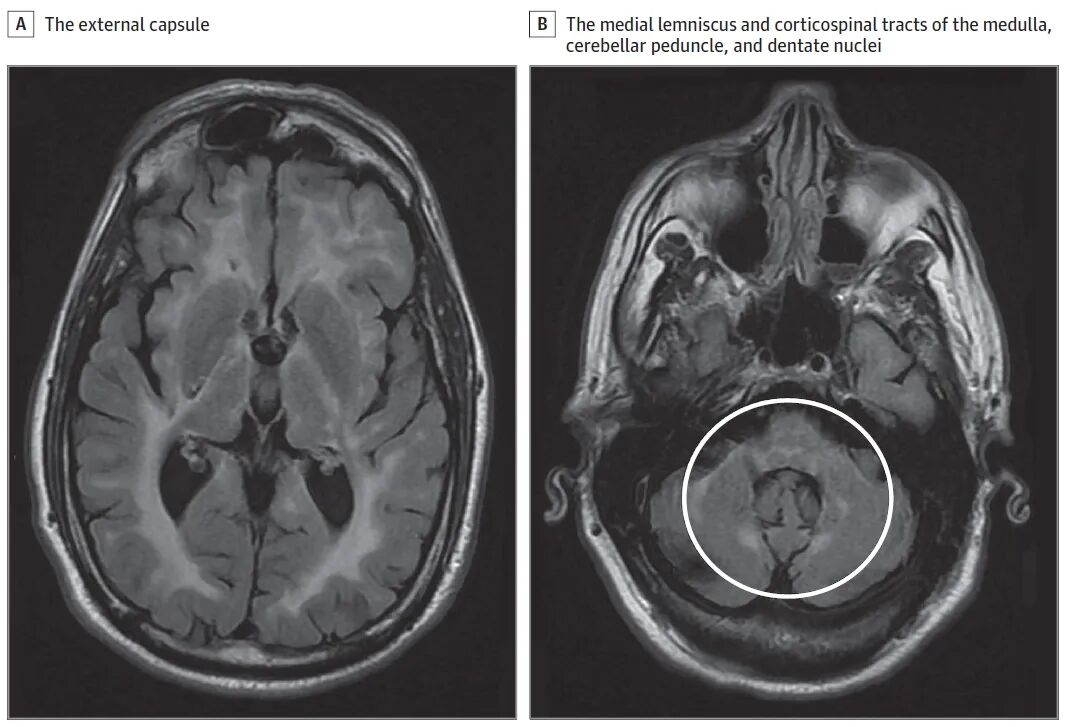

图.脑MRI显示FLAIR高信号,涉及脑室周围区、皮质脊髓束、内囊后肢、外囊(A)、延髓内侧丘系和皮质脊髓束、小脑脚和齿状核(B,圆圈)。

一名61岁男性患者因慢性进行性无力和步态功能障碍前来就诊。四年前,他出现了进行性手臂和腿部无力。随后,他因步态失衡、脚绊倒而反复跌倒,并伴有尿失禁。一年前,他的妻子注意到他出现进行性记忆力减退(例如,去熟悉的地方时迷路)、构音障碍和不恰当的笑声(即在没有明确情绪触发的情况下不由自主地笑)。他有高血压病史。家族中没有已知的神经系统疾病史。他的母系有阿什肯纳兹犹太血统。没有已知的近亲婚配史。神经系统检查显示短期回忆受损(5分钟后无法回忆起5个单词中的任何一个)和假性延髓情绪(pseudobulbar affect)。颅神经检查显示痉挛性构音障碍,但无舌肌萎缩/肌束震颤。上下肢均有痉挛,手部内在肌和小腿肌肉萎缩,双侧手部内在肌和下肢远端肌肉轻度无力。下肢远端大纤维感觉减退。Romberg征阴性。肱二头肌和膝腱反射为3+,踝反射消失。双侧跖反射呈伸肌反应。小脑功能正常。步态呈痉挛性。脑磁共振成像(MRI)显示脑室周围白质融合性T2/FLAIR高信号,累及皮质脊髓束、内囊后肢、外囊、脑桥和髓质的内侧丘系和皮质脊髓束(图)。颈、胸段脊髓MRI显示弥漫性萎缩,无信号异常。肌电图显示慢性感觉运动轴索神经病和腰骶神经根病。维生素B12、甲基丙二酸、铜、维生素E、乳酸/丙酮酸、极长链脂肪酸、血浆/尿氨基酸和溶酶体酶水平正常,胆汁酸谱正常,感染血清学阴性(HIV、梅毒和人类T淋巴细胞病毒)。脑脊液分析显示细胞计数、蛋白质和葡萄糖水平、寡克隆条带谱和IgG指数正常。

APBD是一种罕见的常染色体隐性遗传性神经退行性疾病,属于IV型糖原累积病谱,由双等位基因致病性GBE1变异引起。临床表现各异,但核心症状包括进行性神经源性膀胱、由于上下运动神经元混合受累(即脊髓神经病)导致的步态功能障碍以及40岁或之后的认知障碍。下运动神经元受累是由于长度依赖性轴索多发性神经病和多发性神经根病所致。在严重病例中,曾有报道出现类似阿尔茨海默病的痴呆表型。进展速度通常较慢。在迄今为止最大的系列研究中,症状出现的中位年龄为51岁,轮椅依赖和死亡的中位年龄分别为63岁和70岁。影像学表现可能不具特异性,包括脑室周围区域、内囊后肢和外囊中广泛的融合对称性T2/FLAIR高信号白质异常。

其他提示APBD的线索(如果存在)包括皮质脊髓束、脑桥和延髓内侧丘系、小脑上脚和齿状核,以及延髓和脊髓萎缩的受累。尽管神经活检可能显示多葡聚糖体,但确诊需要通过靶向GBE1测序、包含GBE1的多基因检测、全外显子组测序或全基因组测序进行基因检测。治疗为支持性治疗,包括痉挛、神经源性膀胱、自主神经功能障碍和认知衰退。